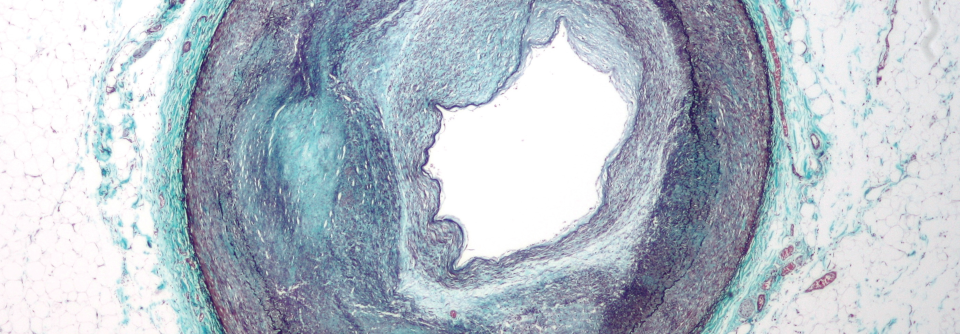

COPD-Patienten scheinen in Bezug auf ihre Lungenerkrankung nicht von niedrigen LDL-Cholesterinwerten zu profitieren. In einer Studie waren diese mit mehr Exazerbationen verbunden.

Was dem Herz guttut, ist möglicherweise ungünstig für die Lunge: COPD-Patienten mit niedrigem LDL-Cholesterin scheinen ein erhöhtes Risiko für schwere Exazerbationen und Todesfälle zu haben. Diesen Zusammenhang ermittelten die Autoren einer dänischen Querschnittstudie aufgrund der registerbasierten Daten von mehr als 100.000 Menschen.

Ihrer Analyse zufolge steigt die Wahrscheinlichkeit für eine akute Verschlechterung der Lungenerkrankung um mehr als 40 % (Hazard Ratio 1,43) bei Vergleich zwischen dem niedrigsten und höchsten LDL-Quartil. Auch der Unterschied zwischen dem zweiten und vierten Quartil war mit einer Differenz von 21 % noch klinisch signifikant. Außerdem erhöhte sich bei geringen LDL-Werten die COPD-bedingte Mortalität.